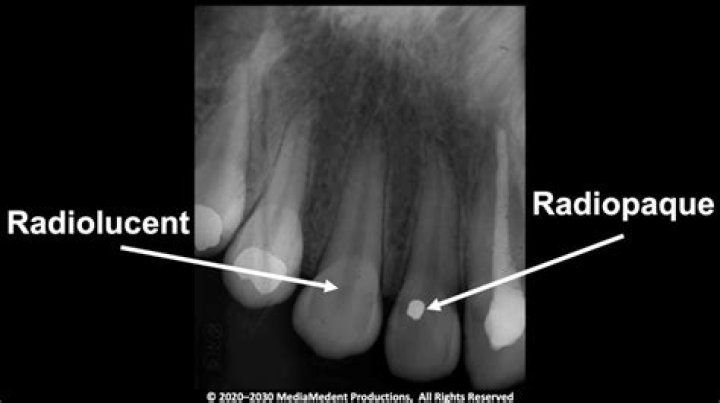

What color is radiolucent? Radiolucent structures appear dark or black in the radiographic image. Radiopaque – Refers to structures that are dense and res...